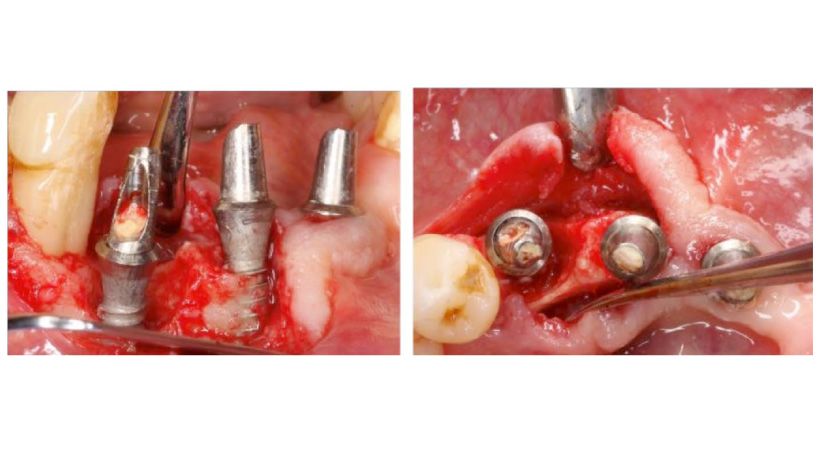

Hay una escasez de estudios que evalúan implantes dentales cortos y estrechos. Este estudio prospectivo tuvo como objetivo evaluar el rendimiento de los implantes dentales cortos (≤8 mm) y estrechos (≤3,5 mm de ancho) que soportan prótesis fijas en el maxilar o mandíbula atrófica. Con ese fin, se incluyeron en el estudio pacientes con implantes cortos. El grupo de control fueron aquellos con implantes dentales largos y estrechos (longitud > 8 mm y diámetro ≤ 3,5 mm). Las variables clínicas y demográficas se extrajeron de las historias clínicas. Durante el seguimiento, se evaluaron y analizaron estadísticamente la supervivencia de los implantes y la pérdida ósea marginal. Se incluyeron cuarenta y un implantes (18 y 23 implantes en los grupos de prueba y control, respectivamente). La mediana del tiempo de seguimiento fue de 26 meses desde su inserción en ambos grupos. Los resultados revelaron que no hubo fallo de implante ni diferencias estadísticamente significativas en términos de pérdida ósea marginal. Solo se produjo un efecto de aflojamiento de tornillo en el grupo de implantes cortos. Los implantes dentales cortos y estrechos podrían ser una alternativa para la restauración de las mandíbulas gravemente reabsorbidas.